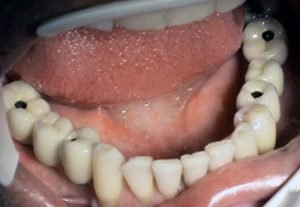

3. PHASE - making a temporary solution

4.PHASE - implant placement

Prosthetic treatment in a toothless jawbone carried - 4 implants